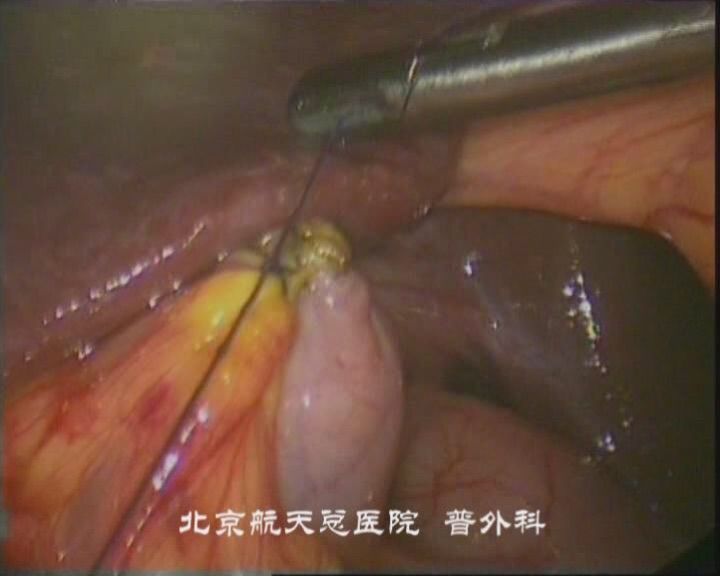

腹腔鏡下保膽取石術(shù):适用(yong)于(yu)單(dan)髮(fa)結石、且膽囊功能(néng)良好、有(yǒu)強烈保膽意願的(de)患者。腔鏡下打開膽囊,可(kě)聯(lian)郃(he)膽道鏡取石,再縫郃(he)膽囊開口。